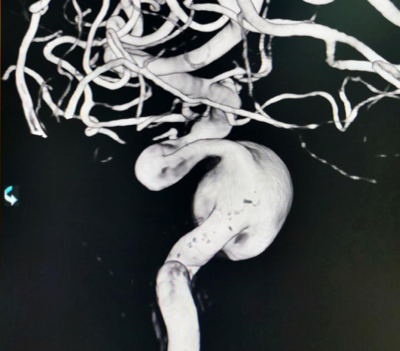

造影见左侧颈内动脉海绵窦段巨大动脉瘤,瘤体远端海绵窦水平段血管狭窄,眼动脉段血管扩张,左侧A1段缺如

术后XperCT提示支架贴壁良好